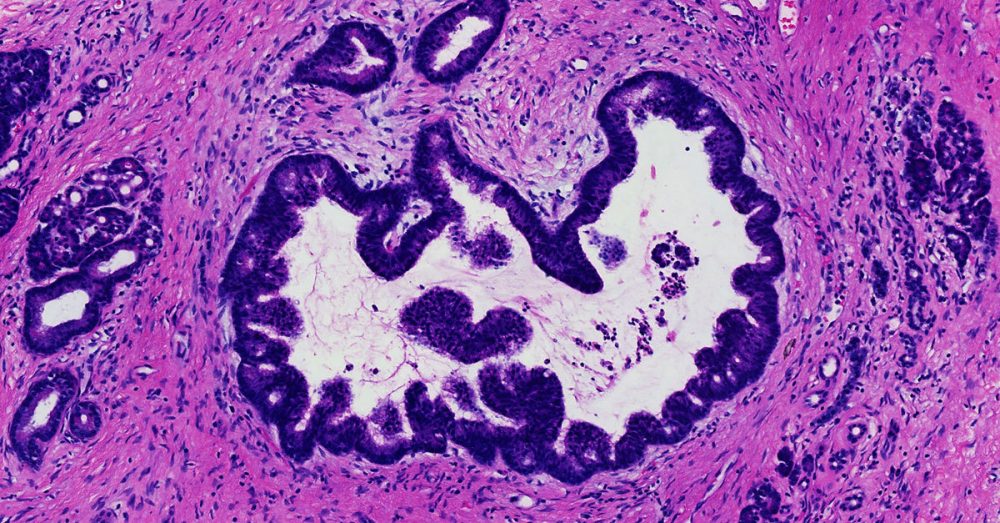

High-grade pancreatic intraepithelial neoplasia replaces the older term- PanIN-3.